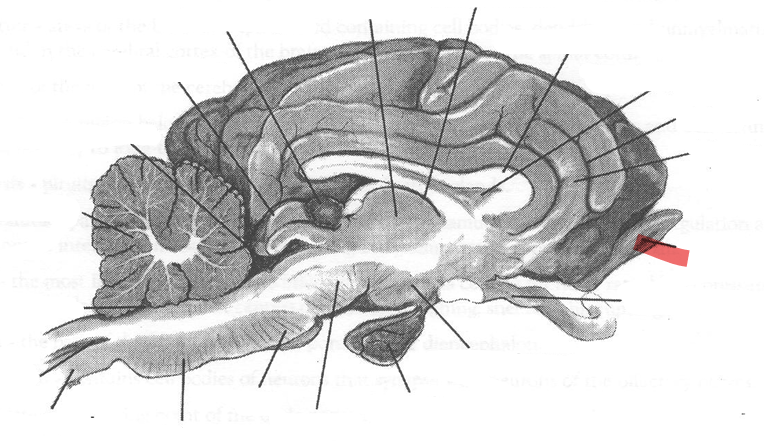

Identify highlighted arrow

Spinal cord

2

New cards

Identify highlighted arrow

Medulla

3

New cards

Identify highlighted arrow

Pons

4

New cards

Identify highlighted arrow

Midbrain

5

New cards

Identify highlighted arrow

Hypophysis

6

New cards

Identify highlighted arrow

Hypothalamus

7

New cards

Identify highlighted arrow

Optic nerve

8

New cards

Identify highlighted arrow

Olfactory bulb

9

New cards

Identify highlighted arrow

Gyrus

10

New cards

Identify highlighted arrow

Sulcus

11

New cards

Identify highlighted arrow

Corpus callosum

12

New cards

Identify highlighted arrow

Third ventricle

13

New cards

Identify highlighted arrow

Thalamus

14

New cards

Identify highlighted arrow

Pineal body

15

New cards

Identify highlighted arrow

cerebellum

16

New cards

Identify highlighted arrow

Fourth ventricle